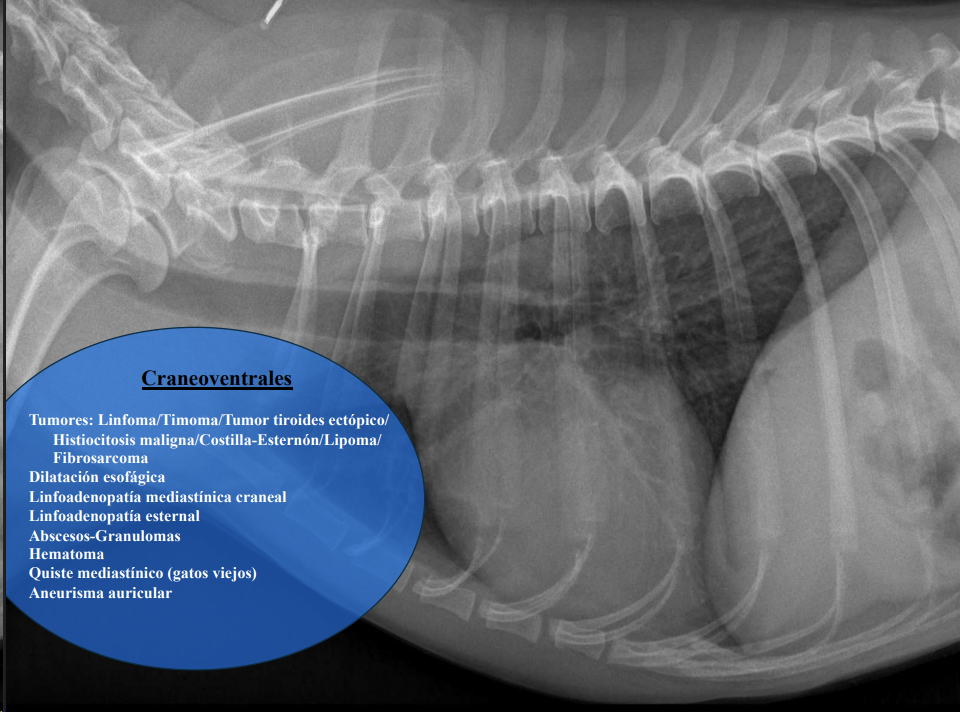

3. Alteraciones de anchura del mediastino craneal

Causas:

- Derrame mediastínico.

- Masas mediastínicas (craneodorsales, hilares, caudodorsales, caudoventrales, craneoventrales).

- Linfomas en gato, timomas en perros.

Craneoventrales: linfoma, timoma, tumor tiroideo, histiocitosis, lipoma, fibrosarcoma, linfoadenopatía esternal o craneal, absceso, aneurisma auricular.